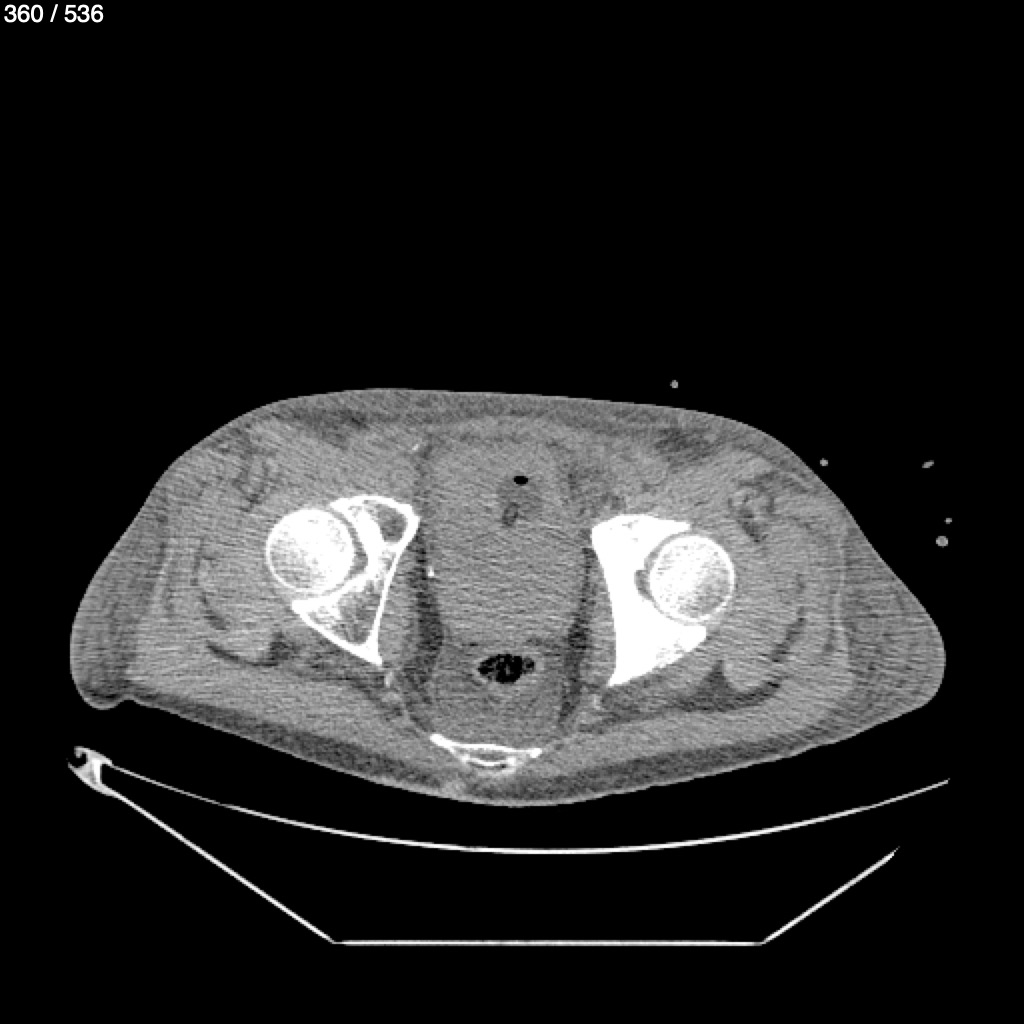

Angel Villalobos Palomeque 73 A - T.C Abdomen Simple